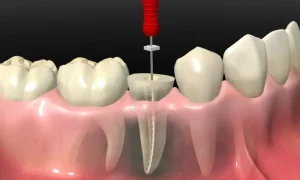

عصب کشی دندان، که در اصطلاح پزشکی به آن درمان ریشه یا اندودانتیکس گفته میشود، یکی از رایجترین و حیاتیترین درمانهای دندانپزشکی میباشد که برای نجات دندانی که پالپ (بافت نرم داخلی حاوی اعصاب و عروق خونی) آن دچار آسیب غیرقابل برگشت یا عفونت شده است، انجام میگردد. عصب کشی دندان در کرج با متخصصان مجرب و کلینیکهای مجهز، انجام میشود.

درمان ریشه شامل مراحل زیر است: